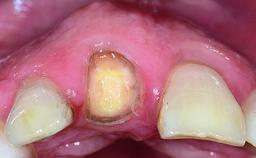

A healthy 28-year-old female patient presented for a consultation on treatment options to restore her upper right central incisor. At the clinical examination, the tooth responded to percussion and palpation. The gingiva was red and slightly swollen, with a mid-facial probing depth of 10 mm. The upper right lateral incisor showed no signs or symptoms, did not respond to exploration and percussion, and the vitality test was positive. The periapical radiograph revealed that tooth 11 had been endodontically treated, with no lesion evident at the apex. A small radiopaque calcified structure surrounded by a narrow radiolucent zone (3 × 3 mm) was present at the apex of tooth 12.

Soft Tissue Contour and Volume Slightly compromised